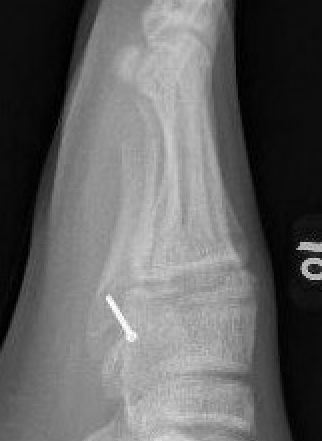

Intramedullary Screw

Screw fixation Zone 2 nonunion

Screw fixation Zone 3 nonunion

Entry point

- 5th metatarsal is not straight

- high and medial to get straight shot

- avoids plantar insertion peroneus brevis

- screw diameter 3.5 / 4.5 / 5.5 / 6.5

- screw threads must be distal to fracture site to allow compression